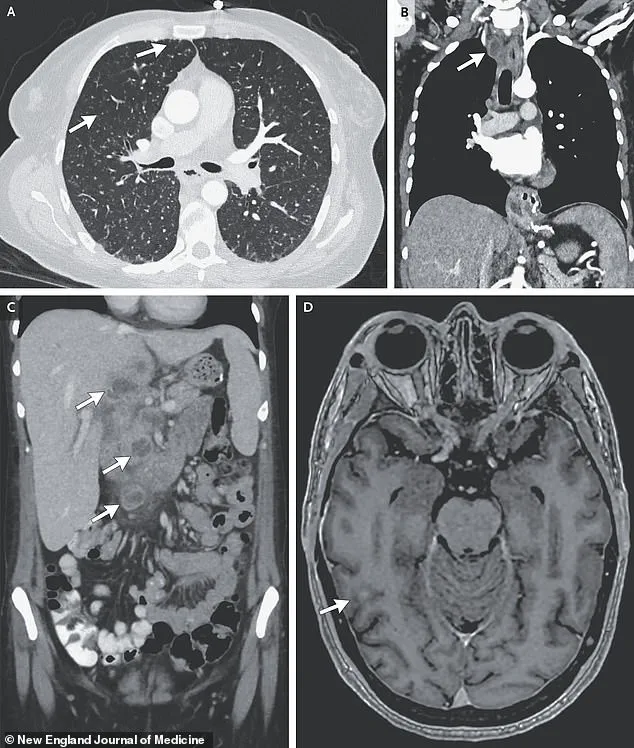

Further imaging and biopsies painted a more sinister picture.

Lesions were detected in her liver, lymph nodes, pancreas, and brain—organs that should have been untouched by the disease.

A recent case study highlights this grim reality: a woman’s scans revealed nodules in her lungs, liver, pancreas, and brain, with an enlarged lymph node in her chest.

These findings, though rare, underscore the disease’s potential to evade detection and wreak havoc on multiple organ systems.